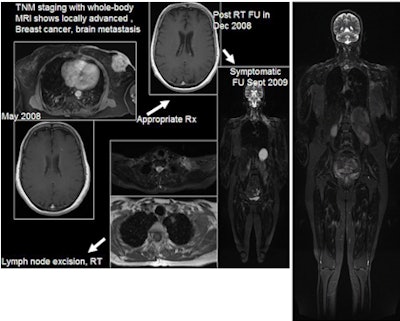

| 61-year-old woman with locally advanced breast cancer underwent whole-body MRI (far right), which revealed a brain metastasis. The patient initiated whole-brain radiation therapy and returned nine months later with neck pain, at which time repeat whole-body MRI showed lymphadenopathy and a solitary lung nodule. MRI is used to guide treatment of the patient, who now has her disease under control. Images courtesy of Dr. Joshita Singh. |